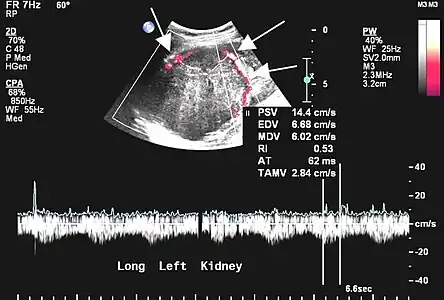

L'échographie est rarement réalisée pour les localisations pleurales, mais peut être utile dans les autres localisations[45]. Les tumeurs fibreuses solitaires se présentent comme des masses homogènes, hypoéchogènes et bien délimitées ; le doppler permet de visualiser la vascularisation. Les tumeurs pleurales se mobilisent avec les mouvements ventilatoires[45].

- Tumeur fibreuse solitaire du rein

Aspect échographique. La vascularisation est visible en rouge, repérée par les flèches[46].